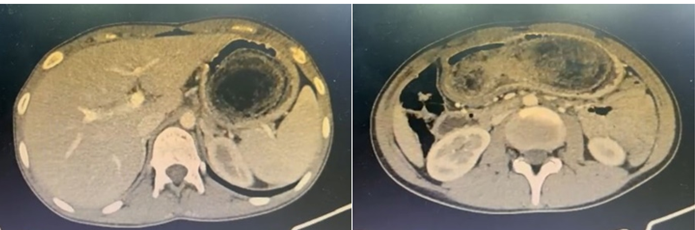

Fig.2 La tomografía computarizada abdominal demostró un estómago dilatado con contenido amorfo en su interior